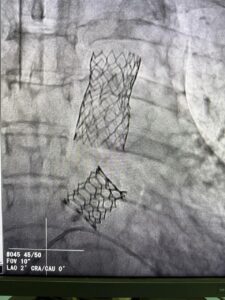

وقال الدكتور حسام عبدالغفار المتحدث الرسمي لوزارة الصحة والسكان، إنه من خلال دعم الدكتور خالد عبدالغفار، نائب رئيس مجلس الوزراء ووزير الصحة والسكان، للجهود المتواصلة التي تبذلها المؤسسة العلاجية لتطوير مستشفياتها والارتقاء بمستوى الرعاية الصحية المقدمة بأعلى مستويات الجودة والكفاءة، مع التركيز على التدريب المستمر للفرق الطبية على أحدث التقنيات والتدخلات الجراحية الدقيقة، نجح الفريق الطبي في زرع الصمام الرئوي داخل صمام نسيجي سابق، لمريض عمره 22 عاما، وهي العملية الأولى من نوعها، التي يتم خلالها وضع صمام، داخل صمام نسيجي سابق، وتركيبه جراحيًا، وهي من التدخلات الدقيقة وشديدة التعقيد.

وأوضح «عبدالغفار» أن الفريق الطبي بمستشفى مبرة مصر القديمة، نجح أيضا في إجراء عملية تغيير الصمام الأورطي عن طريق القسطرة بتقنية (تافي)، لمريض عمره 69 عاماً، يعاني من ضيق شديد بالشريان الأورطي النازل، حيث تم تغيير الصمام ثم عمل توسيع للشريان الأورطي وتركيب دعامة، وهي من العمليات الدقيقة جدا، مشيرا إلى أن الطاقم الطبي نجح في علاج 37 مريضا بواسطة هذا التدخل شديد التعقيد .